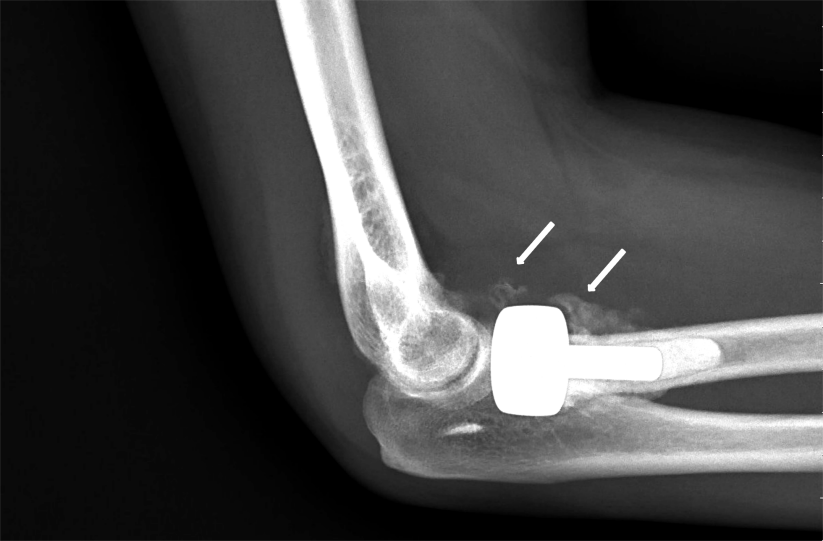

近期,我科就收治了一位肘部创伤术后HO伴关节活动障碍的患者。患者戴某,男,43岁,因外伤致左桡骨小头、尺骨冠状突骨折行左侧桡骨小头置换术后HO伴关节活动受限1月余门诊收治入院,经查体患者左肘屈曲、伸直、前臂旋转均严重受限,伴有明显疼痛及肿胀,日常生活及参与能力受限。

图1:肘关节X光检查结果